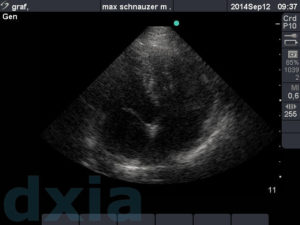

Imágenes obtenidas durante el estudio ecocardiográfico

paraesternal max

Paraesternal derecho eje largo

No se observa dilatación de cámaras cardíacas. Septo IV normal. Válvulas mitrálica y tricuspídea normoimplantadas y sin alteraciones morfológicas.